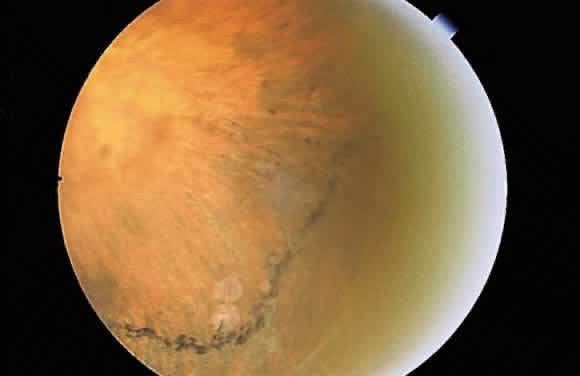

Fig. 12. Section of the eye showing subretinal hemorrhage. (Courtesy of Ralph C. Eagle Jr, MD, Philadelphia, PA) Fig. 12. Section of the eye showing subretinal hemorrhage. (Courtesy of Ralph C. Eagle Jr, MD, Philadelphia, PA)